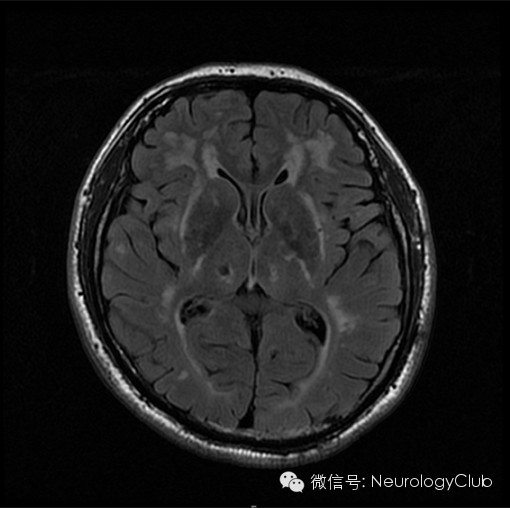

★ 在MRI的T2像表现为大小不一的高信号,不累及弓状纤维,主要位于侧脑室周围和深部白质。以额叶白质最常受累,其次为颞叶和顶叶,而枕叶受损程度相对较轻。

★ 外囊、颞极的对称性异常信号对诊断有高度提示作用。

(颞极对称性T2/FLAIR高信号)

(外囊对称性T2/FLAIR高信号)